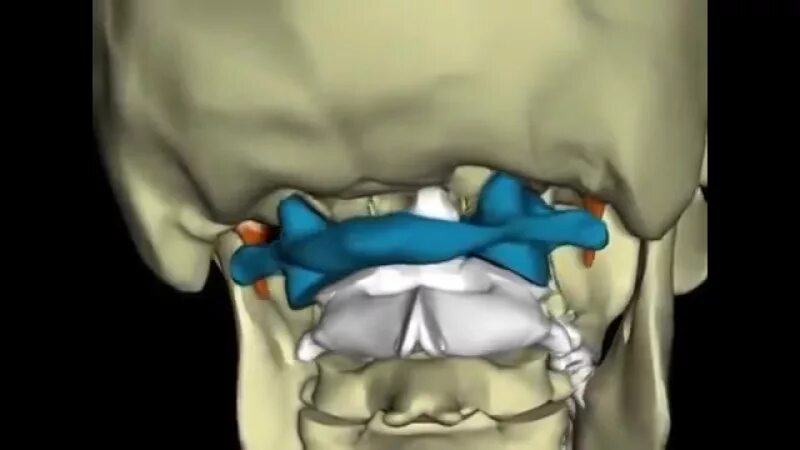

Шейный подвывих у взрослых